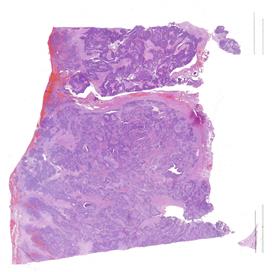

Il carcinoma sieroso ad alto grado dell’ovaio rappresenta una delle neoplasie ginecologiche più aggressive, con un alto tasso di recidiva e una sopravvivenza a lungo termine ancora limitata, nonostante i progressi terapeutici degli ultimi anni. I biomarcatori predittivi di risposta al trattamento, tra cui l’espressione del recettore dei folati (FRα), stanno emergendo come strumenti essenziali per personalizzare le terapie e migliorare gli esiti clinici delle pazienti. Il progetto nasce con l’intento di promuovere un apprendimento interattivo, coinvolgendo i partecipanti in attività mirate al miglioramento dei processi diagnostici e operativi. I patologi, infatti, rivestono un ruolo fondamentale nell’identificazione e caratterizzazione dei biomarcatori predittivi, contribuendo all’ottimizzazione dei percorsi terapeutici. L’evento, strutturato in due incontri online, si pone come obiettivo quello di fornire ai partecipanti gli strumenti teorici e pratici per l’esecuzione, la valutazione e l’interpretazione dei test di espressione dei biomarcatori. L’intento è quello di promuovere un approccio diagnostico sempre più integrato e personalizzato, ponendo l’accento sull’importanza di mantenere standard qualitativi elevati e monitorare nel tempo il proprio lavoro. Per raggiungere questo obiettivo formativo verranno messi a disposizione dei partecipanti kit specifici per esercitarsi nel perseguire la qualità e verificarla nel tempo. I risultati verranno poi discussi nella puntata finale del percorso.

OVAIO

2025 B 01440 A3 EE